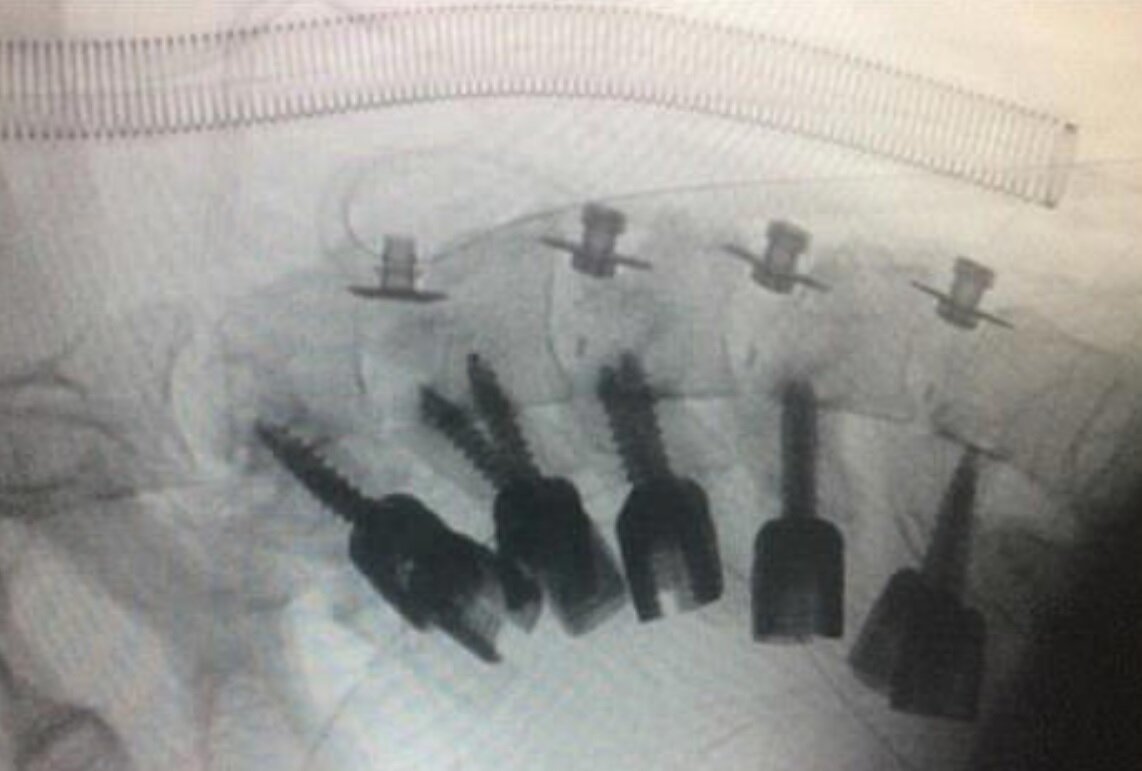

اسکن گردن وی از تغییر شکل و جابجایی مهره های گردن و همچنین در قسمت فوقانی ستون فقرات وی ، بافت آسیب دیده و آسیب دیده خبر داد. همه این مشکلات نشان داد که گردن برای مدت طولانی کشیده و غیر طبیعی است.

پزشکان بر روی گردن جوان تر عمل می کنند و گردن خود را در استخوان های گردن خود اصلاح می کنند.